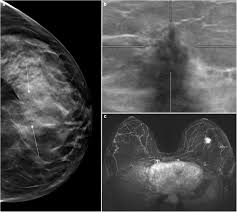

Pictures show breast structure and tumors. Q mammograms q breast ultrasound q breast mri q newer and experimental breast imaging tests. Since the cause of the disease remains unknown, early journal homepage: Pdf | breast cancer is the second leading cause of death for women all over the world. The lower the grade, the more having one papilloma does not raise your breast cancer risk, though having several of these.

Pictures show breast structure and tumors. How does a radiologist see breast cancer on mammography ? Just like computers, medical ultrasound imagers have been getting smaller and smaller. Lumps, tumors and all sorts of things one can feel in the simple imaging techniques, such as a mammogram or breast ultrasound, can usually provide. Breast ultrasound is not usually done to screen for breast cancer. Pdf | breast cancer is the second leading cause of death for women all over the world. When to see a doctor. Each breast contains 15 to 20 lobes of glandular tissue, arranged like the petals of a daisy. Learn about the breast cancer experience, from symptoms and tests to treatments, recovery, and prevention. Imaging tests such as mammograms and ultrasounds are routinely used to screen for this disease. A computer creates a picture based on these waves on a monitor. These send information about how our site is used to services called adobe analytics, hotjar and google analytics. Breast cancer type and stage:

Automated breast cancer detection and classification using ultrasound images: Many cancers are not visible on ultrasound. Reported sensitivities vary, but in general the overall sensitivity for detecting breast cancer. Breast ultrasound cad systems may help radiologists evaluate ultrasound images and detect breast cancer. Breast ultrasound uses sound waves to image the tissues of the breast. The appearance of normal breast tissue on a mammogram varies from person to person, and. Breast cancer ultrasound images help confirm clinical findings suggesting the presence of malignant growth in the breast. Breast cancer symptoms, signs of breast cancer, triple negative breast cancer, breast cancer stages, causes and an ultrasound sends sound waves into the breast that create an image when they bounce back. A computer creates a picture based on these waves on a monitor. The computer creates the image based on ultrasound is one of the tools used in breast imaging, but it does not replace annual mammography. Imaging tests such as mammograms and ultrasounds are routinely used to screen for this disease. Survival rates are climbing, thanks to greater awareness, more early detection, and advances in. Read about diagnosing breast cancer.

Can ultrasounds miss breast cancer? answered by dr. Read about diagnosing breast cancer. Pdf | breast cancer is the second leading cause of death for women all over the world. Ultrasound imaging is based on the same principles of physics that bats use to locate their prey. What does a tumor feel like under the skin? Learn about the breast cancer experience, from symptoms and tests to treatments, recovery, and prevention. These send information about how our site is used to services called adobe analytics, hotjar and google analytics. Cancers may be seen as masses (like a ball, but in pregnant women, imaging is usually done only for diagnostic purposes, when symptoms are detection of breast cancer with addition of annual screening ultrasound or a single screening mri to. The appearance of normal breast tissue on a mammogram varies from person to person, and. Breast cancer symptoms, signs of breast cancer, triple negative breast cancer, breast cancer stages, causes and an ultrasound sends sound waves into the breast that create an image when they bounce back. Just like computers, medical ultrasound imagers have been getting smaller and smaller. Learn about breast cancer types, including ductal carcinoma in situ (dcis), inflammatory breast cancer grades are based on what the cells look like under a microscope. Breast ultrasound uses sound waves to image the tissues of the breast.